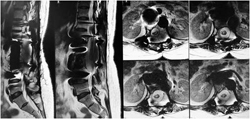

图3-1,CT矢状面和冠状面重建,显示病变为成骨性,病变内有点状钙化。

图3-2,CT横断面显示病变累及L2-L3水平椎骨。

图3-3,MRI矢状面及冠状面显示病变侵入椎管明显压迫硬膜囊和马尾神经

图3-4,MRI横断面显示病变存在软组织成分,在左侧L2-3椎间孔区肿瘤累及椎管内外,明显压迫马尾神经,并且包绕左侧L2神经根。

我们的做法是,住院后立即给予20%甘露醇静滴250mlQ8h,地塞米松20mgQd。第二天患者下肢肌力明显恢复到4级。于是行CT引导下穿刺活检,病理提示病变为“软骨肉瘤”。

软骨肉瘤是恶性程度较高的原发骨肿瘤。应实施整块切除。文献报告,任何形式的经瘤切除都会导致极高的复发率。因此,此例病人应该实施整块切除手术。根据Boriani的WBB分期设计手术策略,由于肿瘤仅仅累及肿瘤左侧的附件和左侧椎体近椎弓根的部分,因此,可以实施矢状切除。但需要做L2和L3两个椎体的矢状切除并且同时切除左侧椎间孔内的L2神经根。由于肿瘤累及左侧椎间孔外侧的软组织,为了直视下游离肿瘤的边界并且结扎并切断左侧L2神经根的远端部分,先从左侧前方入路完成上述任务,而且可以同时切除L1-3和L3-4的椎间盘前份和前纵韧带。然后再行后路手术,游离椎旁肌内的肿瘤,分块切除未被肿瘤累及的右侧椎板、横突、关节突和椎弓根,切除L1-2和L3-4椎间盘的后份,然后经L2和L3椎弓根向椎体前方实施截骨,将L2和L3椎体及附件的左侧的肿瘤组织充分游离,此时结扎并切断L2神经根从硬膜囊发出的部分,从而将肿瘤一整块地切除。

图3-6,肿瘤累及左侧的L2神经根;WBB分期和手术设计。